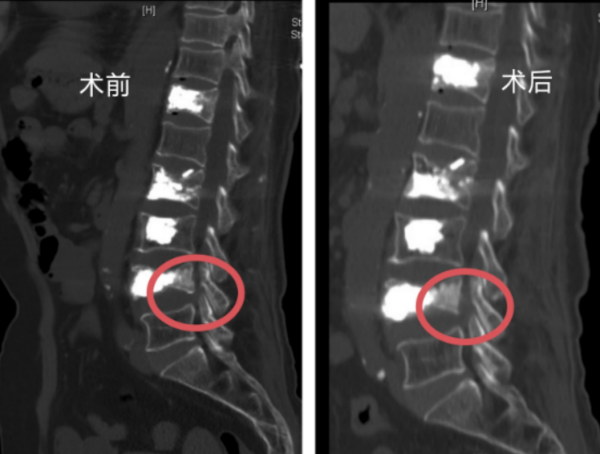

核磁影像术前术后骨块对比

立博体育 脊柱外科一区主任许宇霞接诊后,综合分析患者腰腿痛应该仍与骨折椎体有关。张纯华入院后接受CT及核磁共振检查,许宇霞发现其腰4椎体下缘近椎间孔处有一活动性骨块,当张纯华站立行走时,骨块因椎间盘形态改变移位,刺激出口神经根,导致她出现腰臀部及左下肢麻、胀、痛症状,且在活动后症状加剧。查明病因后,许宇霞主任团队很快为老人实施了椎间孔镜下腰椎减压术,取出了部分骨块,松解了受压的神经根,手术顺利完成。

“脊柱骨折后一定要完善相关检查,很多患者认为做了X线检查后,再做核磁共振、CT检查是重复检查,费钱又费时间。需要明白的是,CT检查可以明确骨折的性质,是否为爆裂骨折,是否有椎体后缘骨块侵入椎管压迫神经,磁共振的优势是可以发现有无神经受压,受压是否严重,这个优势是无法替代的。”许宇霞强调,该患者就是在做了核磁共振及CT后,确诊有活动性骨块移位到椎间孔,压迫了坐骨神经。诊断明确后,即可在椎间孔镜下解决问题。